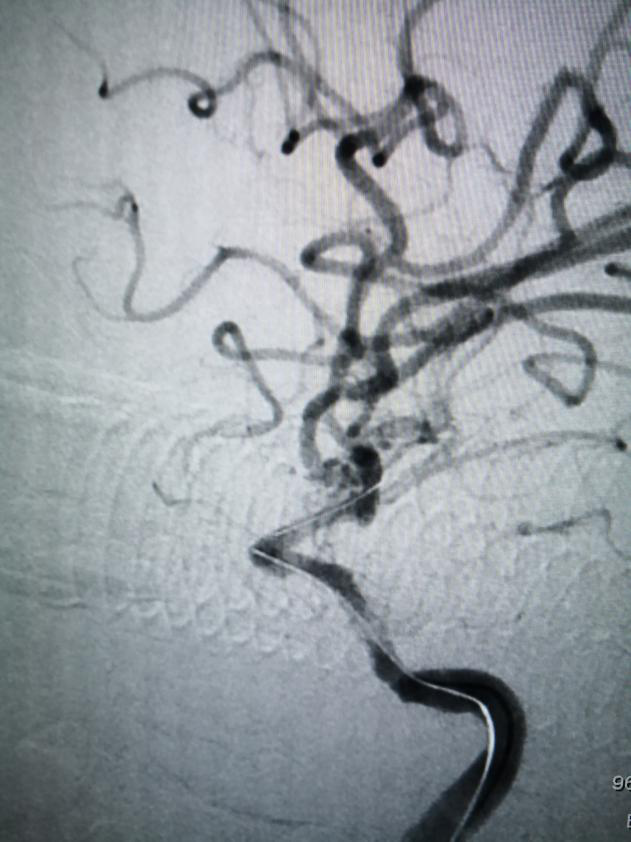

经患者家属同意后,重医附二院派驻石柱分院神经内科宋敏博士、石柱分院神经内科主任李品军副主任医师为患者行脑动脉造影检查,发现患者颈内动脉末端C6段闭塞,实施经导管颅内血管开通术十动脉支架置入术,血管成形,闭塞血管开通,术后患者右侧肢体力量恢复明显,能自行下地行走,能简单的言语表达,其他症状也有明显改善。